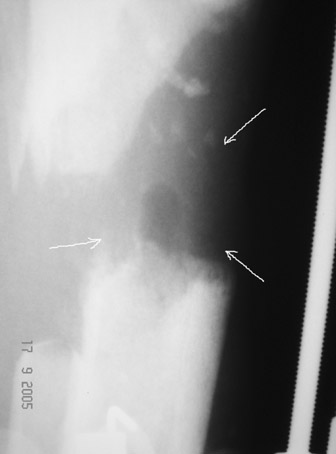

Рентгенологически определяется дистракционный регенерат удовлетворительной плотности и наличие в нем полости (now 1;2;3).

После последнего R- снимка 4 дня назад, аппарат переведен в режим фиксации.